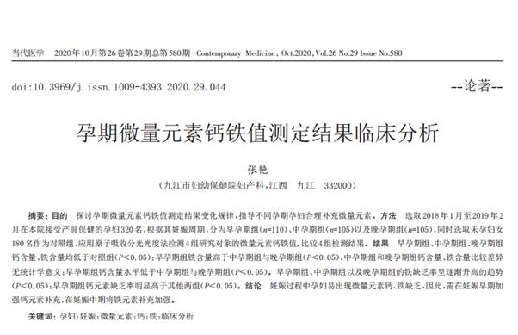

《当代医学》320名孕妇数据:妊娠过程易出现钙铁缺乏

2020年10月,国家级期刊《当代医学》刊发了《孕期微量元素钙铁值测定结果临床分析》,分析结果是基于九江市妇幼保健院妇产科自2018年1 月至2019年2月,抽样320名孕妇,针对孕期微量元素水平进行研究调查的数据。结果显示:妊娠过程中孕妇易出现钙铁缺乏,因此需在妊娠早期加强钙元素的补充,在妊娠中期加强铁元素补充。